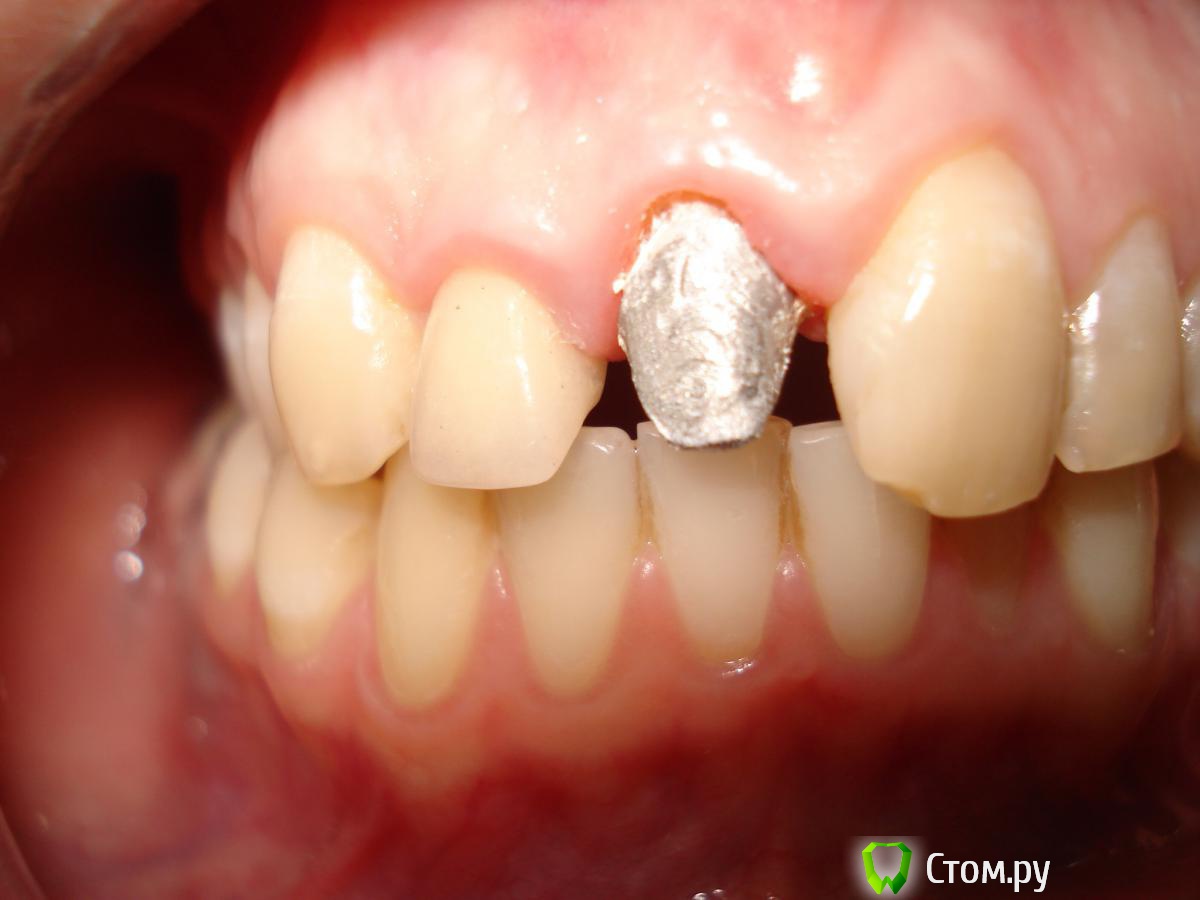

StomDoc Опубликовано 26 ноября, 2013 Поделиться Опубликовано 26 ноября, 2013 Пациентка обратилась с жалобой на скол 11 зуба, доктор поставил метал вкладку но уступа практически нет так же как и на 12 где м/к коронка и вкладка планирую поднять зениты на 11 и 12 зубах тем самым получить хоть какой то минимальный феррул. Какое ваше мнение? И если ставить циркон на передние зубы нужно можно ли их поставить на метал вкладку?? Ссылка на комментарий

M@estro Опубликовано 26 ноября, 2013 Поделиться Опубликовано 26 ноября, 2013 Можно и на вкладку,но сложнее для техника. Зениты все равно у 1.2 и 1.1 поднимать. Моё мнение - она придёт со сколом Вашей работы к другому доктору. Нужна ортодонтия,чтобы убрать причину. Ссылка на комментарий

StomDoc Опубликовано 26 ноября, 2013 Автор Поделиться Опубликовано 26 ноября, 2013 Причина скола не в неправильном прикусе а при депульпировании зубов убрали много тканей и поставили большие пломбы!!! Ссылка на комментарий